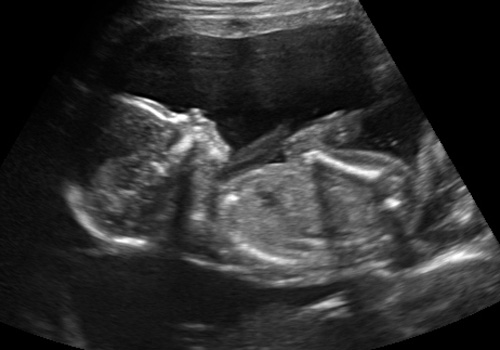

Here's some profile shots of the quadruplets:

Baby A, girl

Baby B, girl

Baby C, boy

Baby D, girl